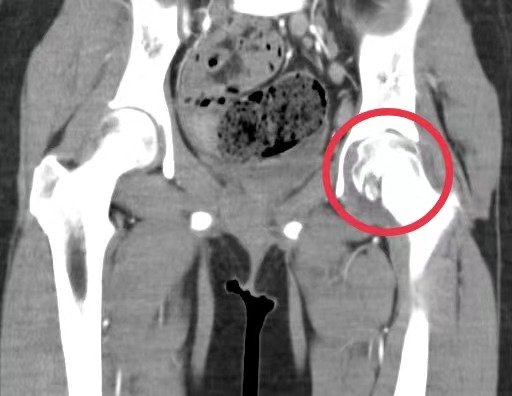

经过相关检查,确诊为髋关节结核。据该医院儿科副主任、副主任医师周海依介绍,明确为左侧髋关节结核、原发性肺结核后,医护团队为孩子制定了抗结核治疗计划,经过精心的治疗和细致的护理,琪琪的病情好转,疼痛的症状逐渐得到控制,目前仍在住院接受治疗。

“骨结核或关节结核前期症状多为疼痛、肿胀、局部功能障碍、关节畸形等,大多数继发于肺结核,是由结核菌侵入骨或关节引起的化脓性破坏性改变,影像学上呈现虫蚀样改变。人体大部分骨骼,尤其是承重骨或关节(脊柱、髋关节、膝关节等),均可被结核菌‘吞噬’。”周海依介绍,该病病程长,常伴有碎骨、死骨、脓肿、瘘管形成甚至功能障碍,严重者出现截瘫,影响孩子们的学习与生活质量。她表示,结核病虽然“可怕”,但其实是“可防可治”的,一旦发现有结核病,一定要进行正规的治疗,骨结核的治疗周期约18-24月,同时还要配合合理的功能训练防止长短腿、关节功能障碍及肌肉废用性萎缩等。